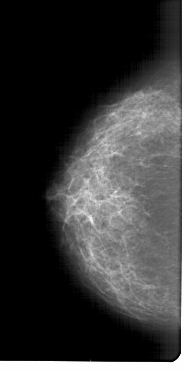

A_1298_1.RIGHT_MLO

RIGHT_MLO LINES 6871 PIXELS_PER_LINE 3346 BITS_PER_PIXEL 12 RESOLUTION 43.5 OVERLAY